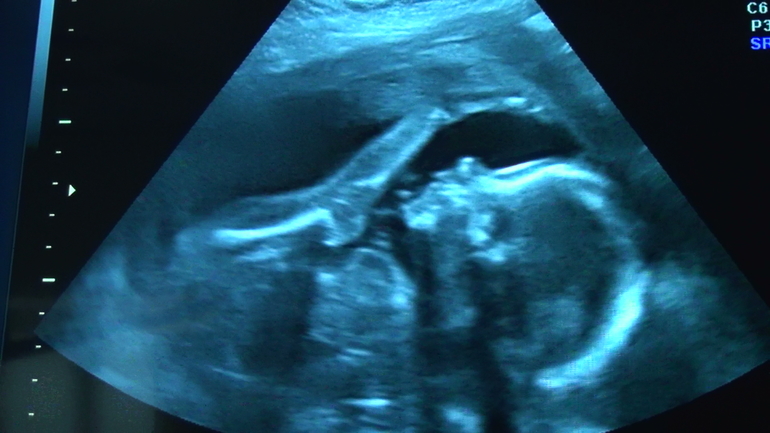

Вот так, только снимок боком повернут)))

У меня ляля то же бьет внизу, но у нас точно головное предлежание. Просто детка лежит в согнутом состоянии и ножки у головы и кулачки там же.На узи видно по этому и толчки у головы))))Иногда она перемещается и распрямляет ножки, бьет возле пупка, но всегда возвращается головой вниз.